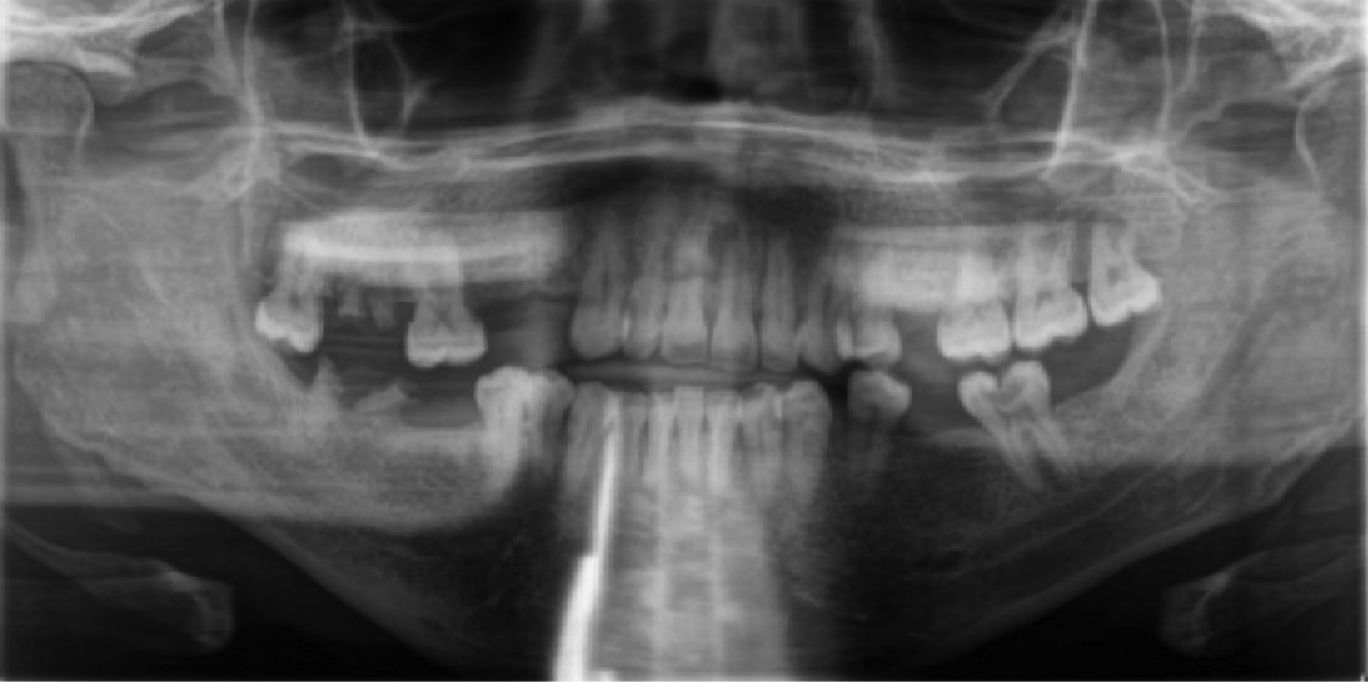

Рентгенологическое обследование включало ортопантомограмму, где было отмечено дистальное смещение зуба 3.5, однако не выявила явных костных разрастаний (показано на фото). Другие находки включали отсутствие нескольких зубов и кариозные поражения. Также наблюдалась потеря кости вокруг нескольких зубов, что соответствовало клинической картине. КЛКТ выявила чётко очерченное образование в области зубов 35 и 36, хорошо визуализируемое как в аксиальных, так и в сагиттальных срезах (показано на фото).

Фото 2. Панорамная рентгенограмма, демонстрирующая смещение зуба 35, кариозное поражение зуба 37, отсутствие нескольких зубов и наличие множественных корней